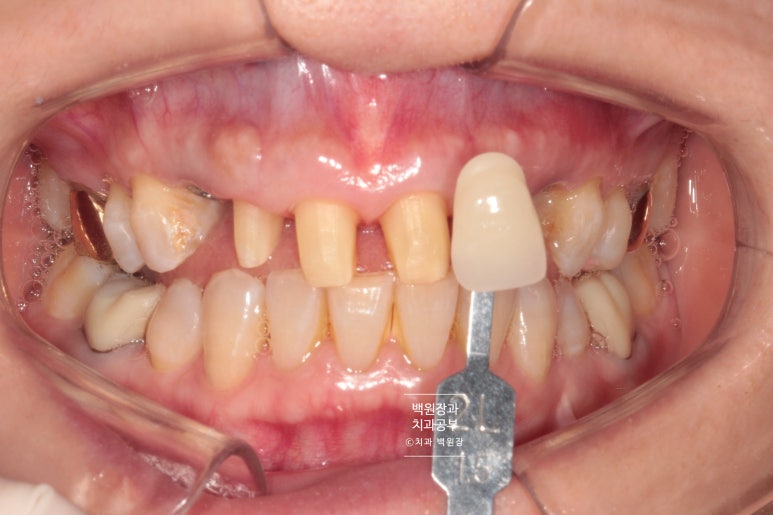

shade guide를 이용하여 제작할 색상을 기록합니다.

Vita shade guide 기준으로

2L 1.5는 조금 밝고 2M 2가 비슷해보이는데요, 원하신다면 앞니 지르코니아 크라운 치료시 보다 더 밝은 색상으로도 제작이 가능합니다! 환자분의 경우 자연스러운 색상을 원하셔서 2M 2로 선택하였습니다!